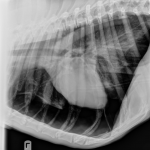

Pneumothorax is a medical condition in which air accumulates in the pleural space (the space between the lung and chest wall), causing the lung to collapse partially or completely. This can lead to breathing difficulties and, in severe cases, life-threatening complications. Pneumothorax Pneumothorax is the accumulation of air in the pleural space with a secondary Pneumothorax is a condition where air collects in the pleural cavity and causes the lung to collapse. Symptoms include chest pain and breathlessness. Surgery is performed in serious cases to remove the blebs or bullaes and re-expand the lung. Explore causes, symptoms, and treatments of pneumothorax in cats to ensure your pet’s health and well-being. When your cat experiences breathing difficulties, it could be a sign of pneumothorax – a serious condition where air accumulates between the lungs and chest wall.

This review article will review treatment and prognosis of spontaneous pneumothorax in dogs and cats. The advantages of surgical and medical management in dogs and cats, as well as current treatment practices, including autologous blood pleurodesis and small-bore chest tubes, will be discussed. Pneumothorax Traumatic pneumothorax is the most frequent type of pneumothorax in dogs. It most often occurs due to blunt trauma (i.e., vehicular accidents, being kicked by a horse), which causes parenchymal pulmonary damage to the lung and a closed pneumothorax. When the thorax is forcefully compressed against a closed glottis, rupture of the lung or bronchial tree

Tension pneumothorax can develop from any type of pneumothorax. However, it is most commonly seen after a traumatic chest injury or in individuals breathing through mechanical ventilation. Traumatic tension pneumothorax Open chest wound, like a stab wound or a gunshot Closed trauma, like a rib fracture Mechanical ventilation High positive pressure during the However, the outlook for many disorders that cause accumulation of fluid in the chest is guarded to poor. Air in the pleural cavity, called pneumothorax, may be caused by trauma or occur spontaneously. The lung collapses if a large volume of air enters the pleural cavity, causing difficulty inhaling or rapid, shallow breathing. Once spontaneous pneumothorax has been diagnosed (discussed in part one of this series) and the patient stabilized, definitive treatment consists of addressing the underlying cause. Dogs commonly develop spontaneous pneumothorax due to bullae or blebs, while cats usually have underlying inflammatory disease, like feline allergic airway disease. As a result,

Definitive treatment of pneumothorax depends on the underlying cause, but there are commonalities across the spectrum of patients who develop this condition. Most dogs require hospitalization until the air accumulation within the chest cavity has stopped or stabilized. Table 1. Summary of current literature about fibrosing pleuritis in dogs and cats. The aim of this case report is to describe clinical presentation, imaging alterations, treatment and outcome in a dog with pneumothorax caused by pleural fibrosis after Learn about the causes, symptoms, and treatment options for dermatitis in dogs. Discover how to keep your furry friend’s skin healthy and comfortable.

What causes a spontaneous pneumothorax? Cystic/bullous lung disease is a common cause of spontaneous pneumothorax in dogs. This includes Pneumothorax can either be large or small, and while small pneumothorax may resolve itself over time, more severe cases always require treatment. Observation is recommended for those with small pneumothorax, and the